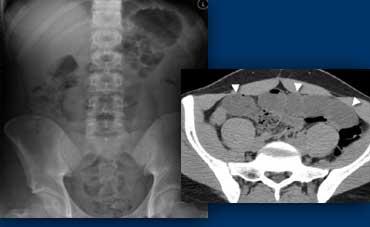

TRÁI: Phim bụng không chuẩn bị ở bệnh nhân bụng cấp, không thấy bất thường. PHẢI: CT thực hiện sau đó cho thấy các quai ruột non giãn (đầu mũi tên) không được nhìn thấy trên phim bụng không chuẩn bị do chúng chỉ chứa đầy dịch mà không có hơi trong lòng ruột.

Tắc ruột có thể không được phát hiện trên phim bụng không chuẩn bị nếu các quai ruột chỉ chứa đầy dịch mà không có hơi trong lòng ruột (hình minh họa).

Ngược lại, nếu phim bụng không chuẩn bị có dấu hiệu gợi ý tắc ruột thì siêu âm hoặc CT thường cần thiết để xác định nguyên nhân.

Do đó, phim bụng không chuẩn bị hiếm khi hữu ích, ngoại trừ trong phát hiện sỏi thận hoặc tràn khí phúc mạc.